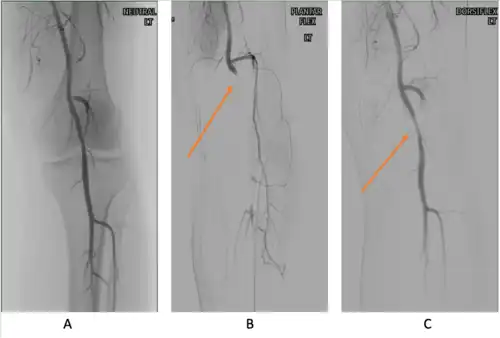

Medical history and physical examination

Provocative maneuvers can be used to improve visualization of PAES on the images.[25] The patient is initially positioned supine with the legs straight, and then instructed to forcefully plantar-flex. A plantarflexion force of 0 to 70 percent maximum has been shown to maximize the sensitivity and specificity for PAES diagnosis.[25] The DU can be a quick, inexpensive, and noninvasive initial screening for PAES. Flow velocities in the popliteal artery will increase, as the popliteal artery is compressed, which is reflected on the DU. If DU is negative but there is still strong suspicion for PAES, MRA or CTA with provocative maneuvers are needed as follow-up imaging. MRA would demonstrate a focal occlusion or narrowing of the mid-popliteal artery, post-stenotic dilatation, or aneurysm of the distal popliteal artery. If MRA or CTA is[13] non-conclusive, DSA may be used as a further option with a high sensitivity (> 97%) for PAES diagnosis.[23]